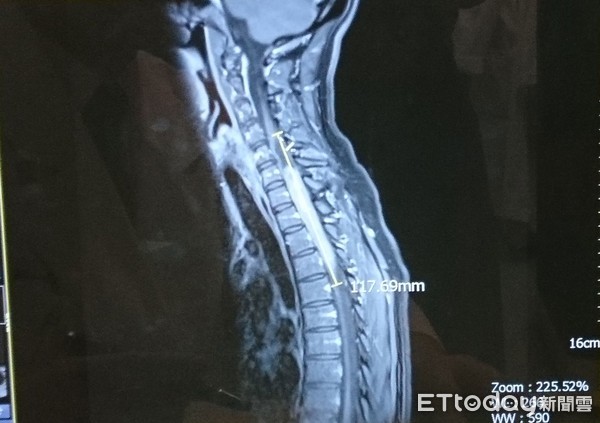

脚酸走路易跌倒! 女长12公分「脊髓瘤」.没医生